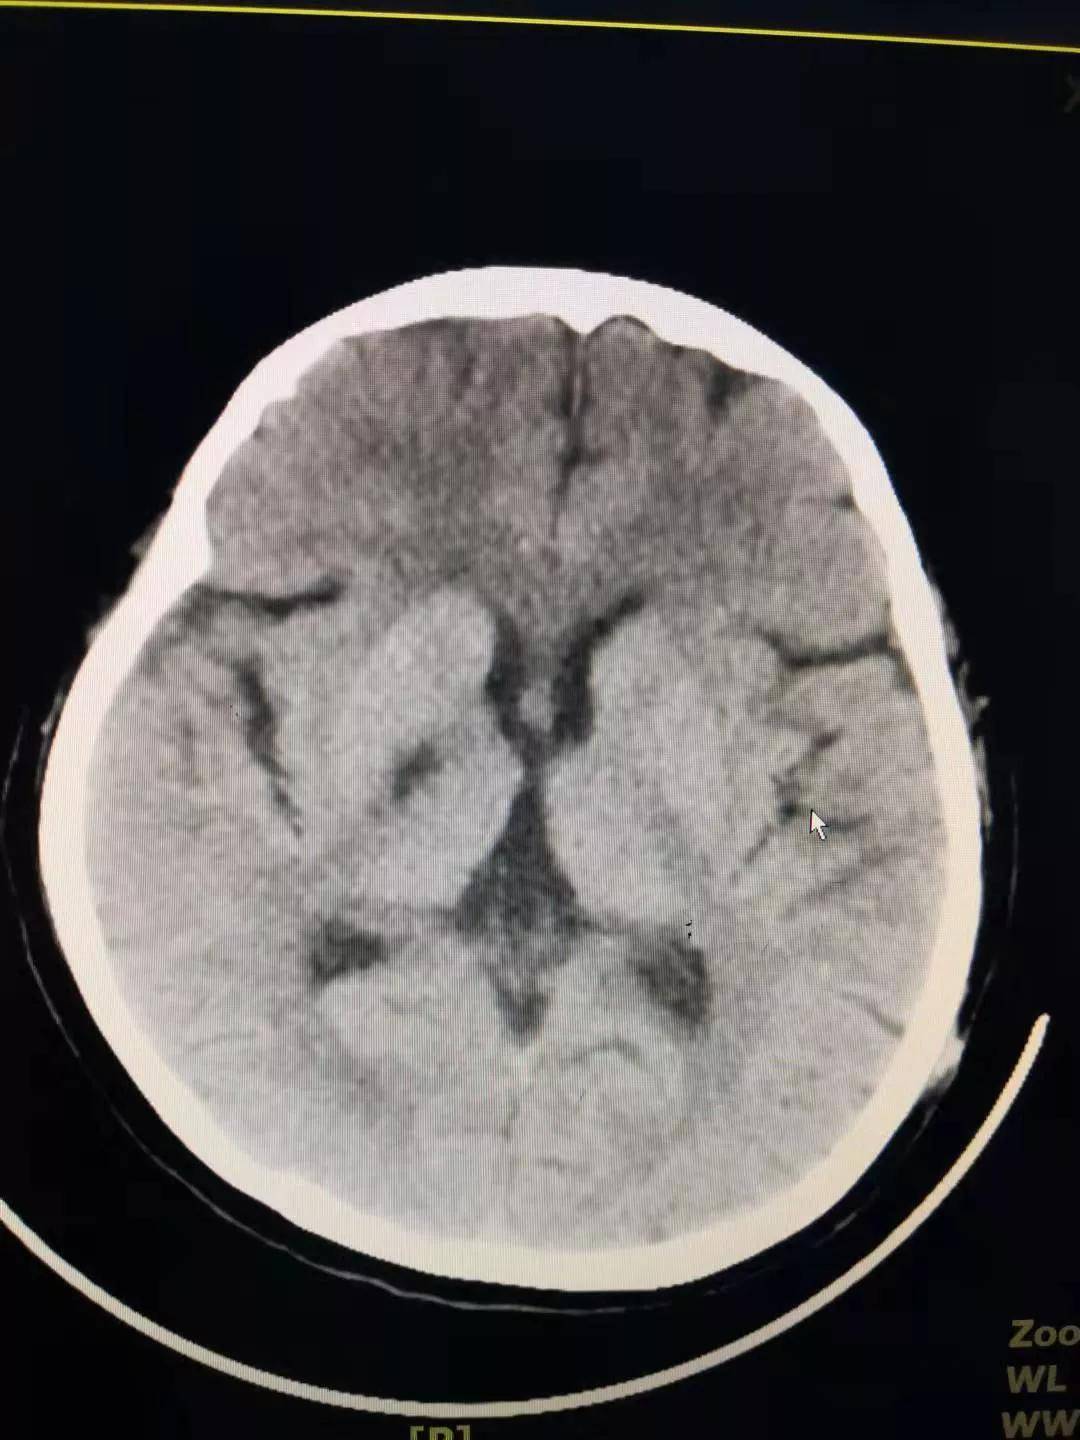

近日 , 60岁的徐女士经人介绍 , 在儿子的陪同下 , 来到西安市中医医院针灸推拿康复科安军明主任医师门诊就诊 。 据徐女士讲 , 自己两天前出现口角歪斜 , 说话不清 , 经多方打听 , 得知西安市中医医院针灸推拿康复科擅长针灸治疗面瘫 , 遂前来求治 。 安军明主任医师仔细询问徐女士病史 , 得知她有5年的糖尿病史和高脂血症病史 , 但否认患有高血压 。 在安军明主任医师耐心追问下 , 徐女士诉自己今晨起床时 , 曾有一过性眩晕、走路向一边倾斜的情况 , 目前现已无大碍 。 安军明主任医师经过望、闻、问、切四诊合参 , 结合患者即刻血压157/85mmHg , 初步诊断为:1.脑梗死 , 2.Ⅱ型糖尿病 , 3.高脂血症 , 4.高血压 。 在安军明主任劝说下 , 徐女士在儿子的陪同下做了头部CT检查 , 很快结果回示 , 正如安军明主任医师诊断的那样 , 徐女士的口角歪斜系基底节区脑梗死所致 , 随即安排其住院治疗 。

中枢性面瘫主要因大脑皮质、内囊、脑桥等部位受损 , 患者出现病灶对侧颜面下部肌肉麻痹 。 主要表现为鼻唇沟变浅 , 露齿时口角下垂 , 不能吹口哨和鼓腮等 , 多见于脑血管病变、脑炎等 。 但患者的眼裂及额纹不受影响,这也是与周围性面瘫的主要区别 。 除面瘫外,中枢性面瘫还有其它表现 , 如肢体麻木、活动障碍、饮水呛咳,失语等 。